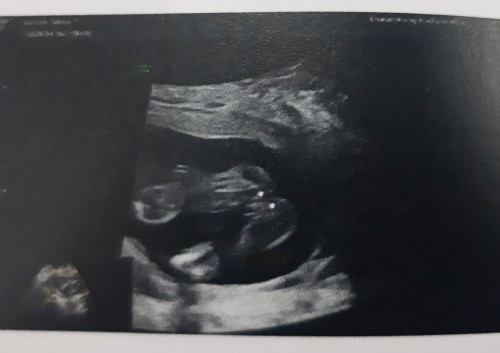

#ท้องแรก 19วีค2วัน